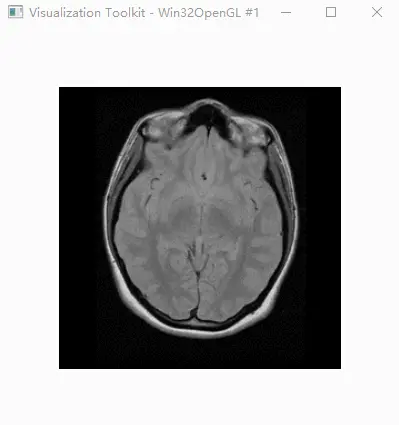

效果

脑部CT图像

在这里插入图片描述